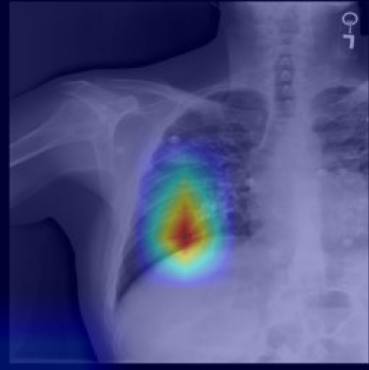

5.2 Visualization of attention weights

Fig. 5 presents a qualitative visualization of the learned word-to-region correspondences facilitated by our AGA framework. The top row shows the original medical images, including both chest X-rays (CXR) and endoscopic ultrasound (EUS) images. The bottom row displays the corresponding heatmaps generated by our model, where warmer colors denote higher activation weights, indicating stronger associations between specific image regions and the given medical concepts. For Atelectasis and Pneumonia, the model focuses on appropriate pulmonary regions, demonstrating strong localization aligned with radiological pathology. For the SMTs domain, terms like low-echoic mass and protruded into the cavity activate precisely the relevant interior structures of the lesion in EUS images. The distinct and interpretable activation patterns validate the effectiveness of our AGA mechanism in achieving fine-grained multimodal alignment.

Atelectasis

Pneumonia